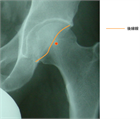

1. 単純X線撮影と読影のポイントを追加し、大腿骨寛骨臼インピンジメント(FAI)の疫学・関節症性変化への進行に関する最新の文献を参考に加筆した。

1. Cam変形は変形性股関節症の発生の危険因子になる(推奨度1、エビデンスランクC、J)